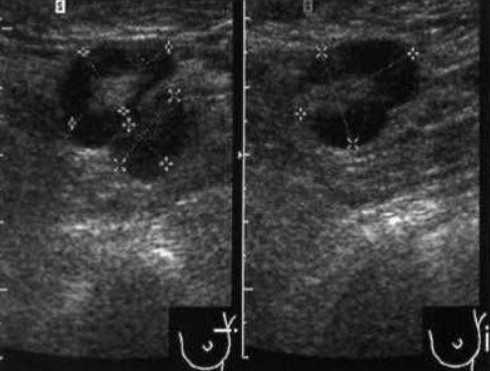

Практически во всех случаях дифференцировали лимфатический узел Кютнера (югулодигастральный), расположенный на границе средней и верхней трети шеи. Выявляемые лимфатические узлы имели размеры от 0,5 х 0,2 см до 2,3 х 0,8 см. УЗ-оценку производили после полипозиционного осмотра и нахождения самой длинной горизонтальной оси, что и принимали за максимальный поперечный диаметр. Большая часть лимфатических узлов (187) имели овальную форму с соотношением поперечного/переднезаднего более 1 (рис. 1 - 3). Тенденцию к округлению имели 30 лимфатических узлов, соотношение поперечного/переднезаднего приближалось к 1.

Мы установили, что, как правило, более округлая конфигурация лимфатического узла при его размерах, превышавших 10 мм, сопровождалась небольшими болевыми ощущениями, и более выраженной простудной (воспалительного характера) симптоматикой. Лимфатические узлы менее 10 мм чаще всего плохо пальпировались, либо вообще не выявлялись пальпаторно. Во всех случаях эхографически хорошо дифференцировался гипоэхогенный кортикальный слой и широкое, средней или чуть ниже средней эхогенности изображение области ворот лимфатических узлов. Четкость дифференциации составных частей лимфатического узла была снижена при размерах менее 5 мм. Мы отмечали различную толщину гипоэхогенного изображения области коры лимфатического узла: от очень широкой - при выраженности или прогрессировании воспалительного процесса, до узкой - на фоне положительной динамики.